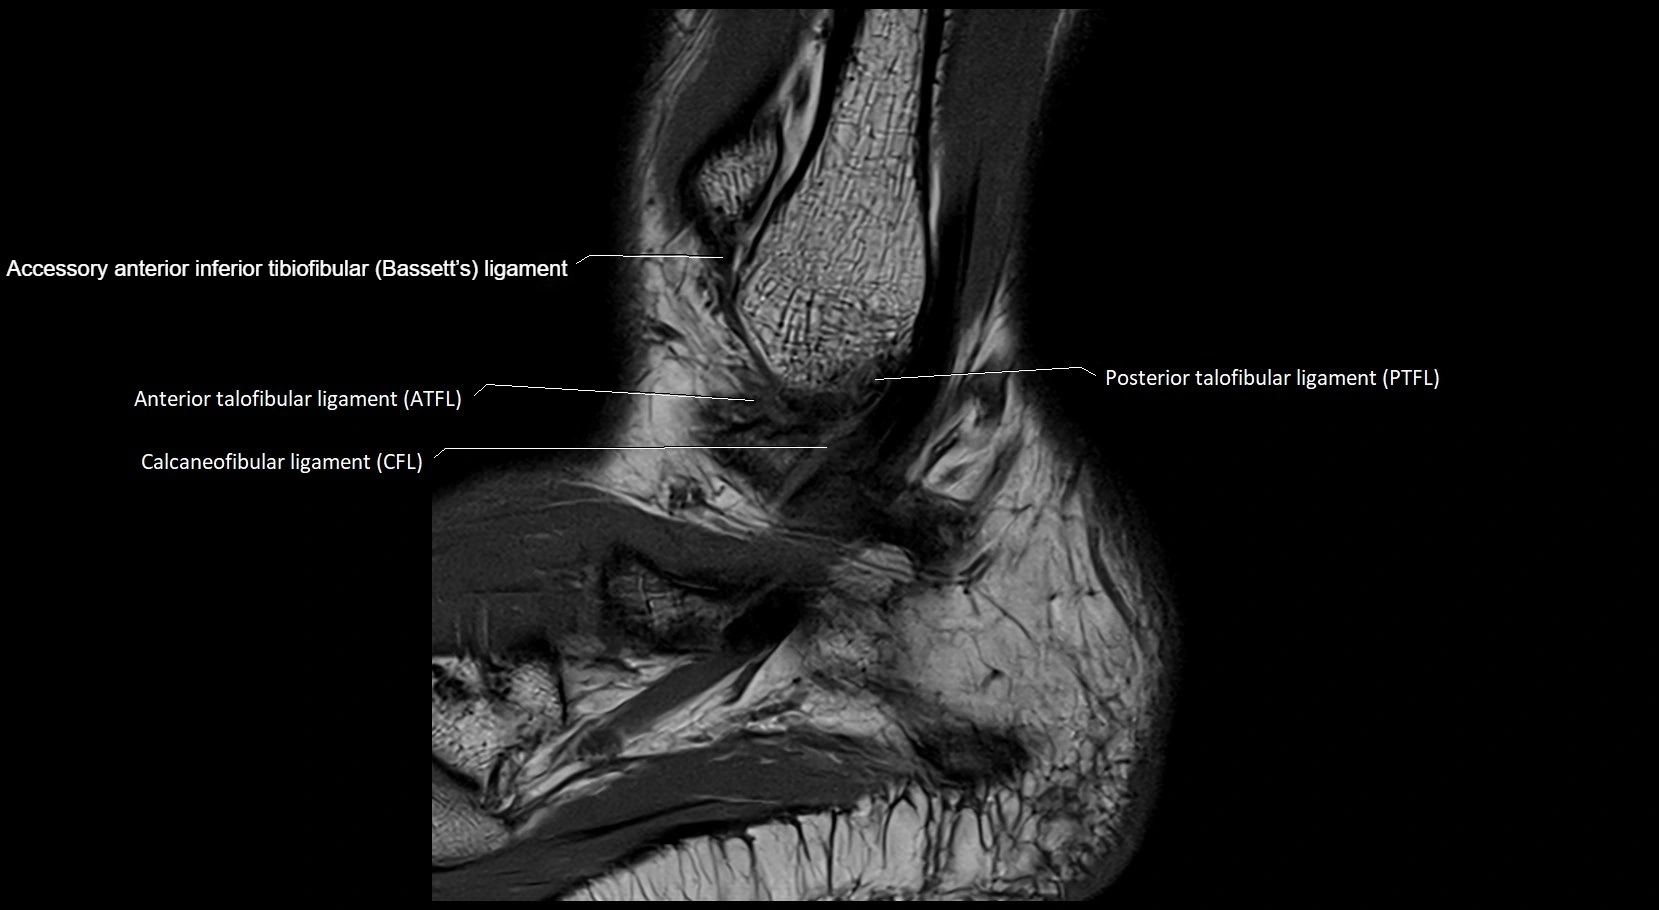

MRI image

image